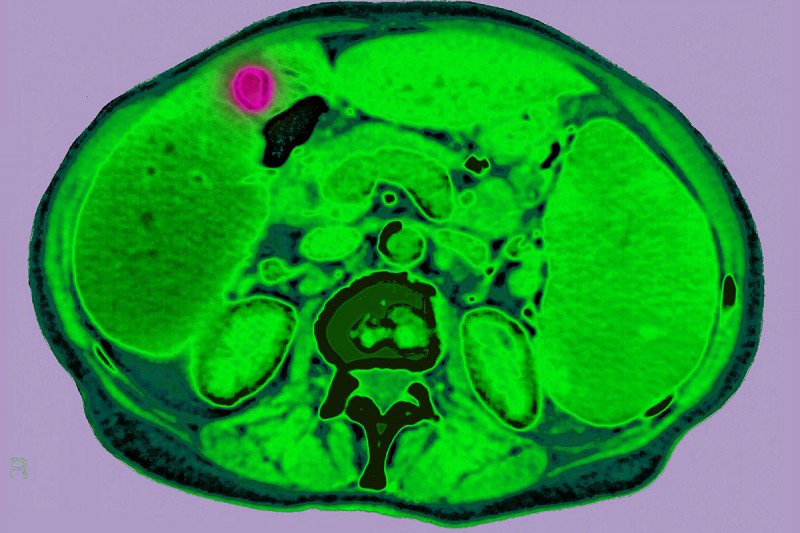

A colorized CT scan showing lymphoma (red) in the abdomen between the liver and the gallbladder. Credit: James Cavallini / Science Photo Library